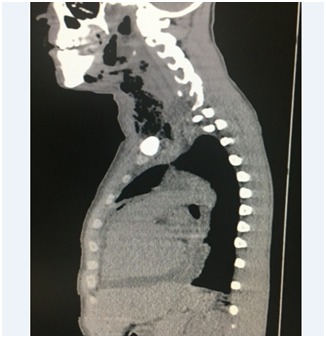

The initial thorax CT (Figure 2) evidenced a considerable increase in the mediastinal planes, with inflammatory areas in the upper and anterior compartments, pleural and pericardial effusion with mediastinal lymph nodes with altered and reactional appearance. The initial cervical CT (Figure 3) showed multiple fluid collections with gaseous foci in the left, parapharyngeal, anterior cervical, right lateral, retropharyngeal and submandibular spaces, with communication between them and a determined extensive mucosal bulging and reduction of the oropharyngeal space. Densification of the muscular planes and glottic region with extensive edema in the visceral space were visualized, characterizing a diffuse and extensive inflammatory process in the cervical region. The patient did not present seropositivity for the HIV virus, exhibited laboratorial values compatible with normal renal function, blood current mixed microbiota with the predominance of Staphyloccuscapitis and sensitivity to all the antibiotics tested, ruling out the presence of super-resistant bacteria. The initial hemogram showed an increased marked number of leukocytes and neutrophils, suggesting a recently established infectious and inflammatory condition. As soon as the diagnostic had been confirmed it was opted for early surgical intervention. The procedures consisted of thoracotomy with the objective of managing pericardial and pleural effusions (Figure 4) to avoid the patient's septic shock; surgical drainage of the right cervical, sublingual, left submandibular, left buccal spaces was also performed plus the extraction of the compromised tooth (Figure 5), indicated as the etiological factor. No airway management surgical procedure was performed. For complete drainage, Penrose and chest drains were installed, which were maintained for 3 and 7 days, respectively. The patient remained sedated for 36 hours postoperatively with or tracheal intubation. The antibiotic therapy of choice was Sodium Piperacillin associated with Tazobactam, 12g and 1.5g per day, respectively. The patient remained under intensive care for 21 days, for postoperative clinical and imaging follow-up control, as well as the remission of signs and symptoms associated with the systemic condition. Currently, the patient is at 6 months of follow-up, in which a satisfactory clinical condition and absence of sequelae are observed.

Figure 2 & 3 CT scans exhibiting liquid collections and extensive cervical and fascial spaces gaseous foci. There are also right interpleural space and pericardial effusion in addition of pulmonary volume reduction of the right lower lobe with focal consolidations and ground glass attenuations.